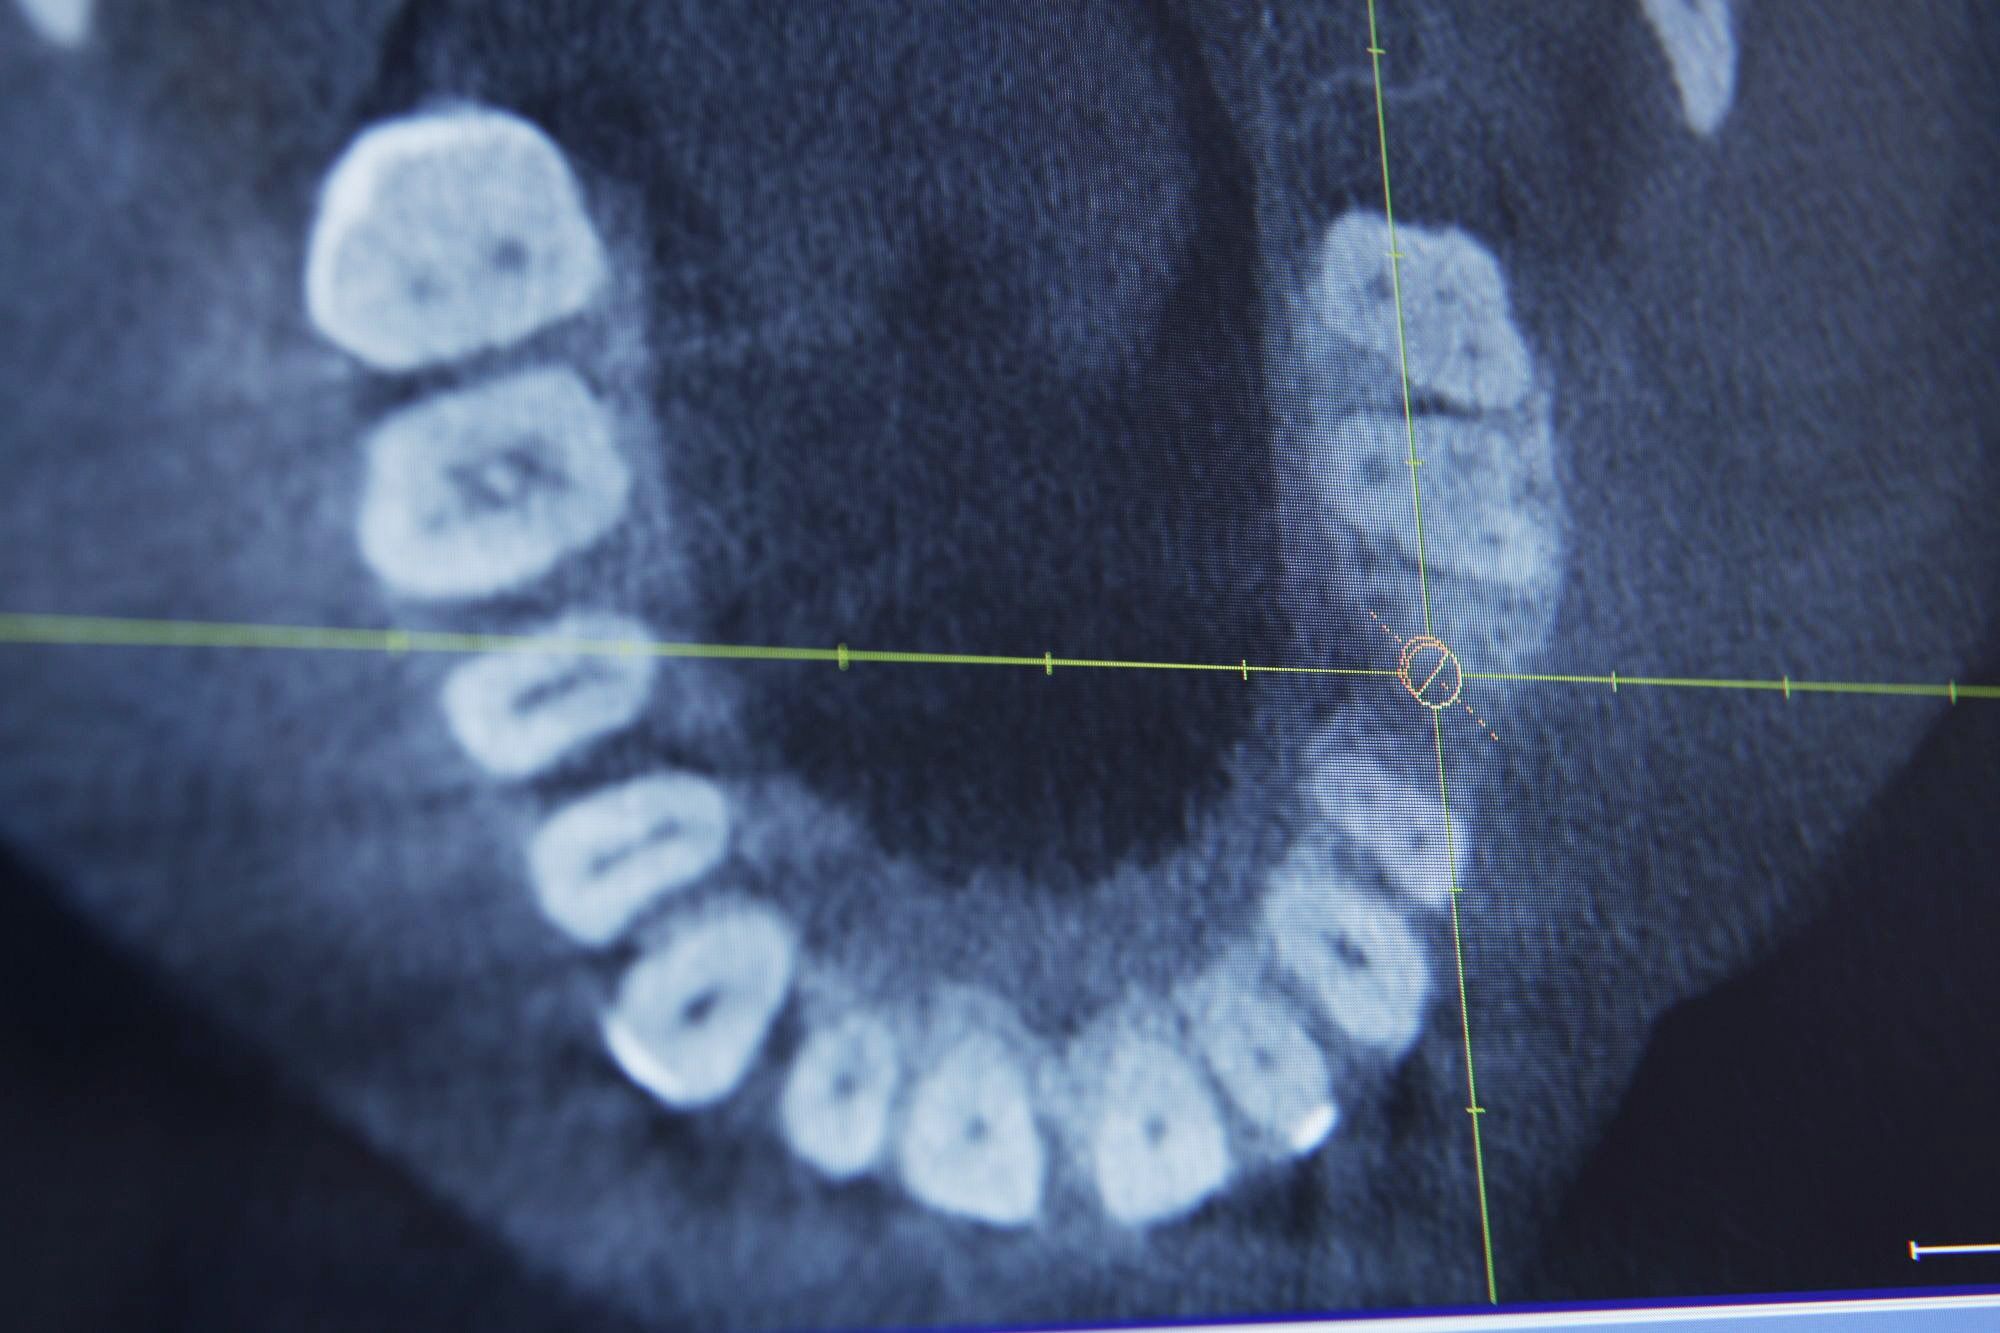

DVT 3D Röntgen­diagnostik

Die Digitale Volumentomographie (DVT) ist eine Weiterentwicklung der Computertomographie. Ähnlich wie beim Computer-Tomogramm (CT) werden bei der digitalen Volumentomographie ( DVT ) Körperbereiche dreidimensional abgebildet. Seit 1999 haben wir auf dem Gebiet der DVT- Untersuchung und Auswertung geforscht, veröffentlicht und Vortragspreise gewonnen.

Während beim CT die untersuchte Region in einzelnen dünnen Schichten gescannt wird, die aneinandergesetzt werden, erfasst die DVT innerhalb weniger Sekunden die gesamte Untersuchungsregion in einem einzigen Umlauf. Daraus resultiert eine um ca. 75-80 Prozent verminderte Strahlendosis bei vergleichbarer Bildqualität. Gleichzeitig treten beim DVT im Gegensatz zum CT kaum Metallartefakte auf, was gerade bei der Darstellung und Diagnostik von Zähnen mit metallischem Zahnersatz oder kieferorthopädischen Brackets der Fall ist.

So können dreidimensionale Bilder des kompletten Gesichtsschädels in kurzer Zeit, ohne Metallartefakte bei gleichzeitig geringer Strahlenbelastung erzeugt werden. Da der Patient nur für wenige Minuten in einem offenen Gerät steht, eignet sich diese Darstellungsmethode für alle Altersklassen!

Durch die dreidimensionale, plastische Darstellung der Gesichtsanatomie inklusive der Kieferhöhlen und des Kauapparats, können außerdem wichtige diagnostische Informationen vor kieferchirurgischen Eingriffen, zur Planung von Implantaten oder kieferorthopädischen Maßnahmen gewonnen werden.